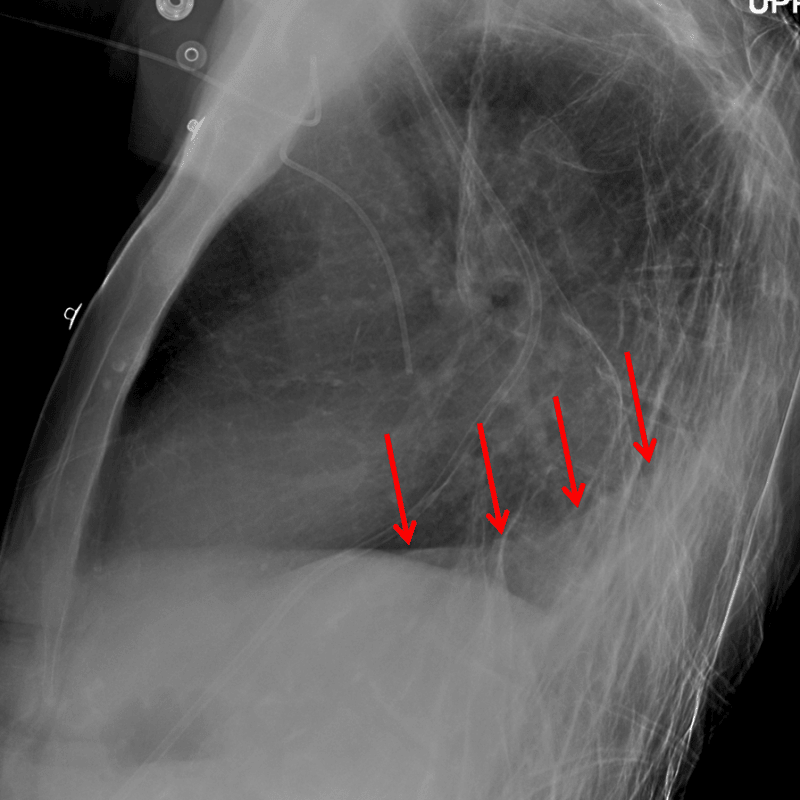

• Triangular opacity at the posteromedial right lung base with loss of the silhouette of the medial and posterior aspect of the right hemidiaphragm

• Evidence of volume loss in the right hemithorax including elevation of the right hemidiaphragm, inferior positioning of the right hilum, rightward mediastinal shift, and crowding of many right ribs

Right lower lobe collapse

• The right lower lobe usually collapses to the inferior/posterior/medial aspect of the right hemithorax, resulting in loss of the medial and posterior silhouette of the right hemidiaphragm. The right heart border silhouette is preserved, which helps distinguish right lower lobe collapse from right middle lobe collapse

Red arrows: right lower lobe collapse.